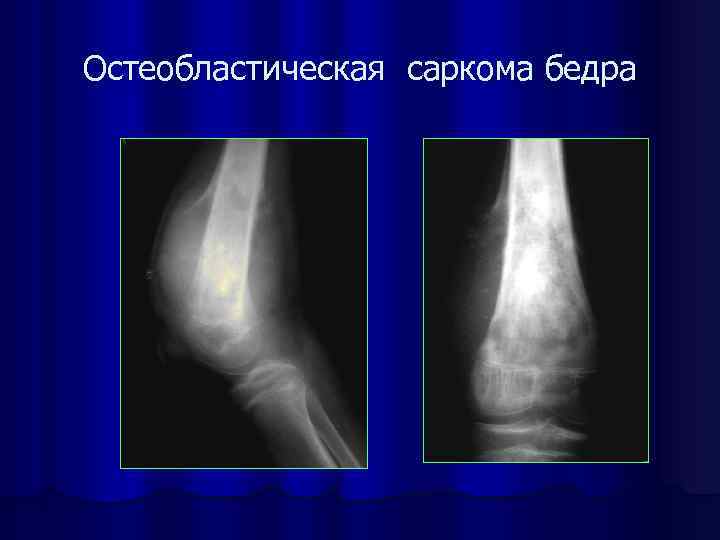

Рентгенологическая картина остеогенной саркомы кости - 98 фото